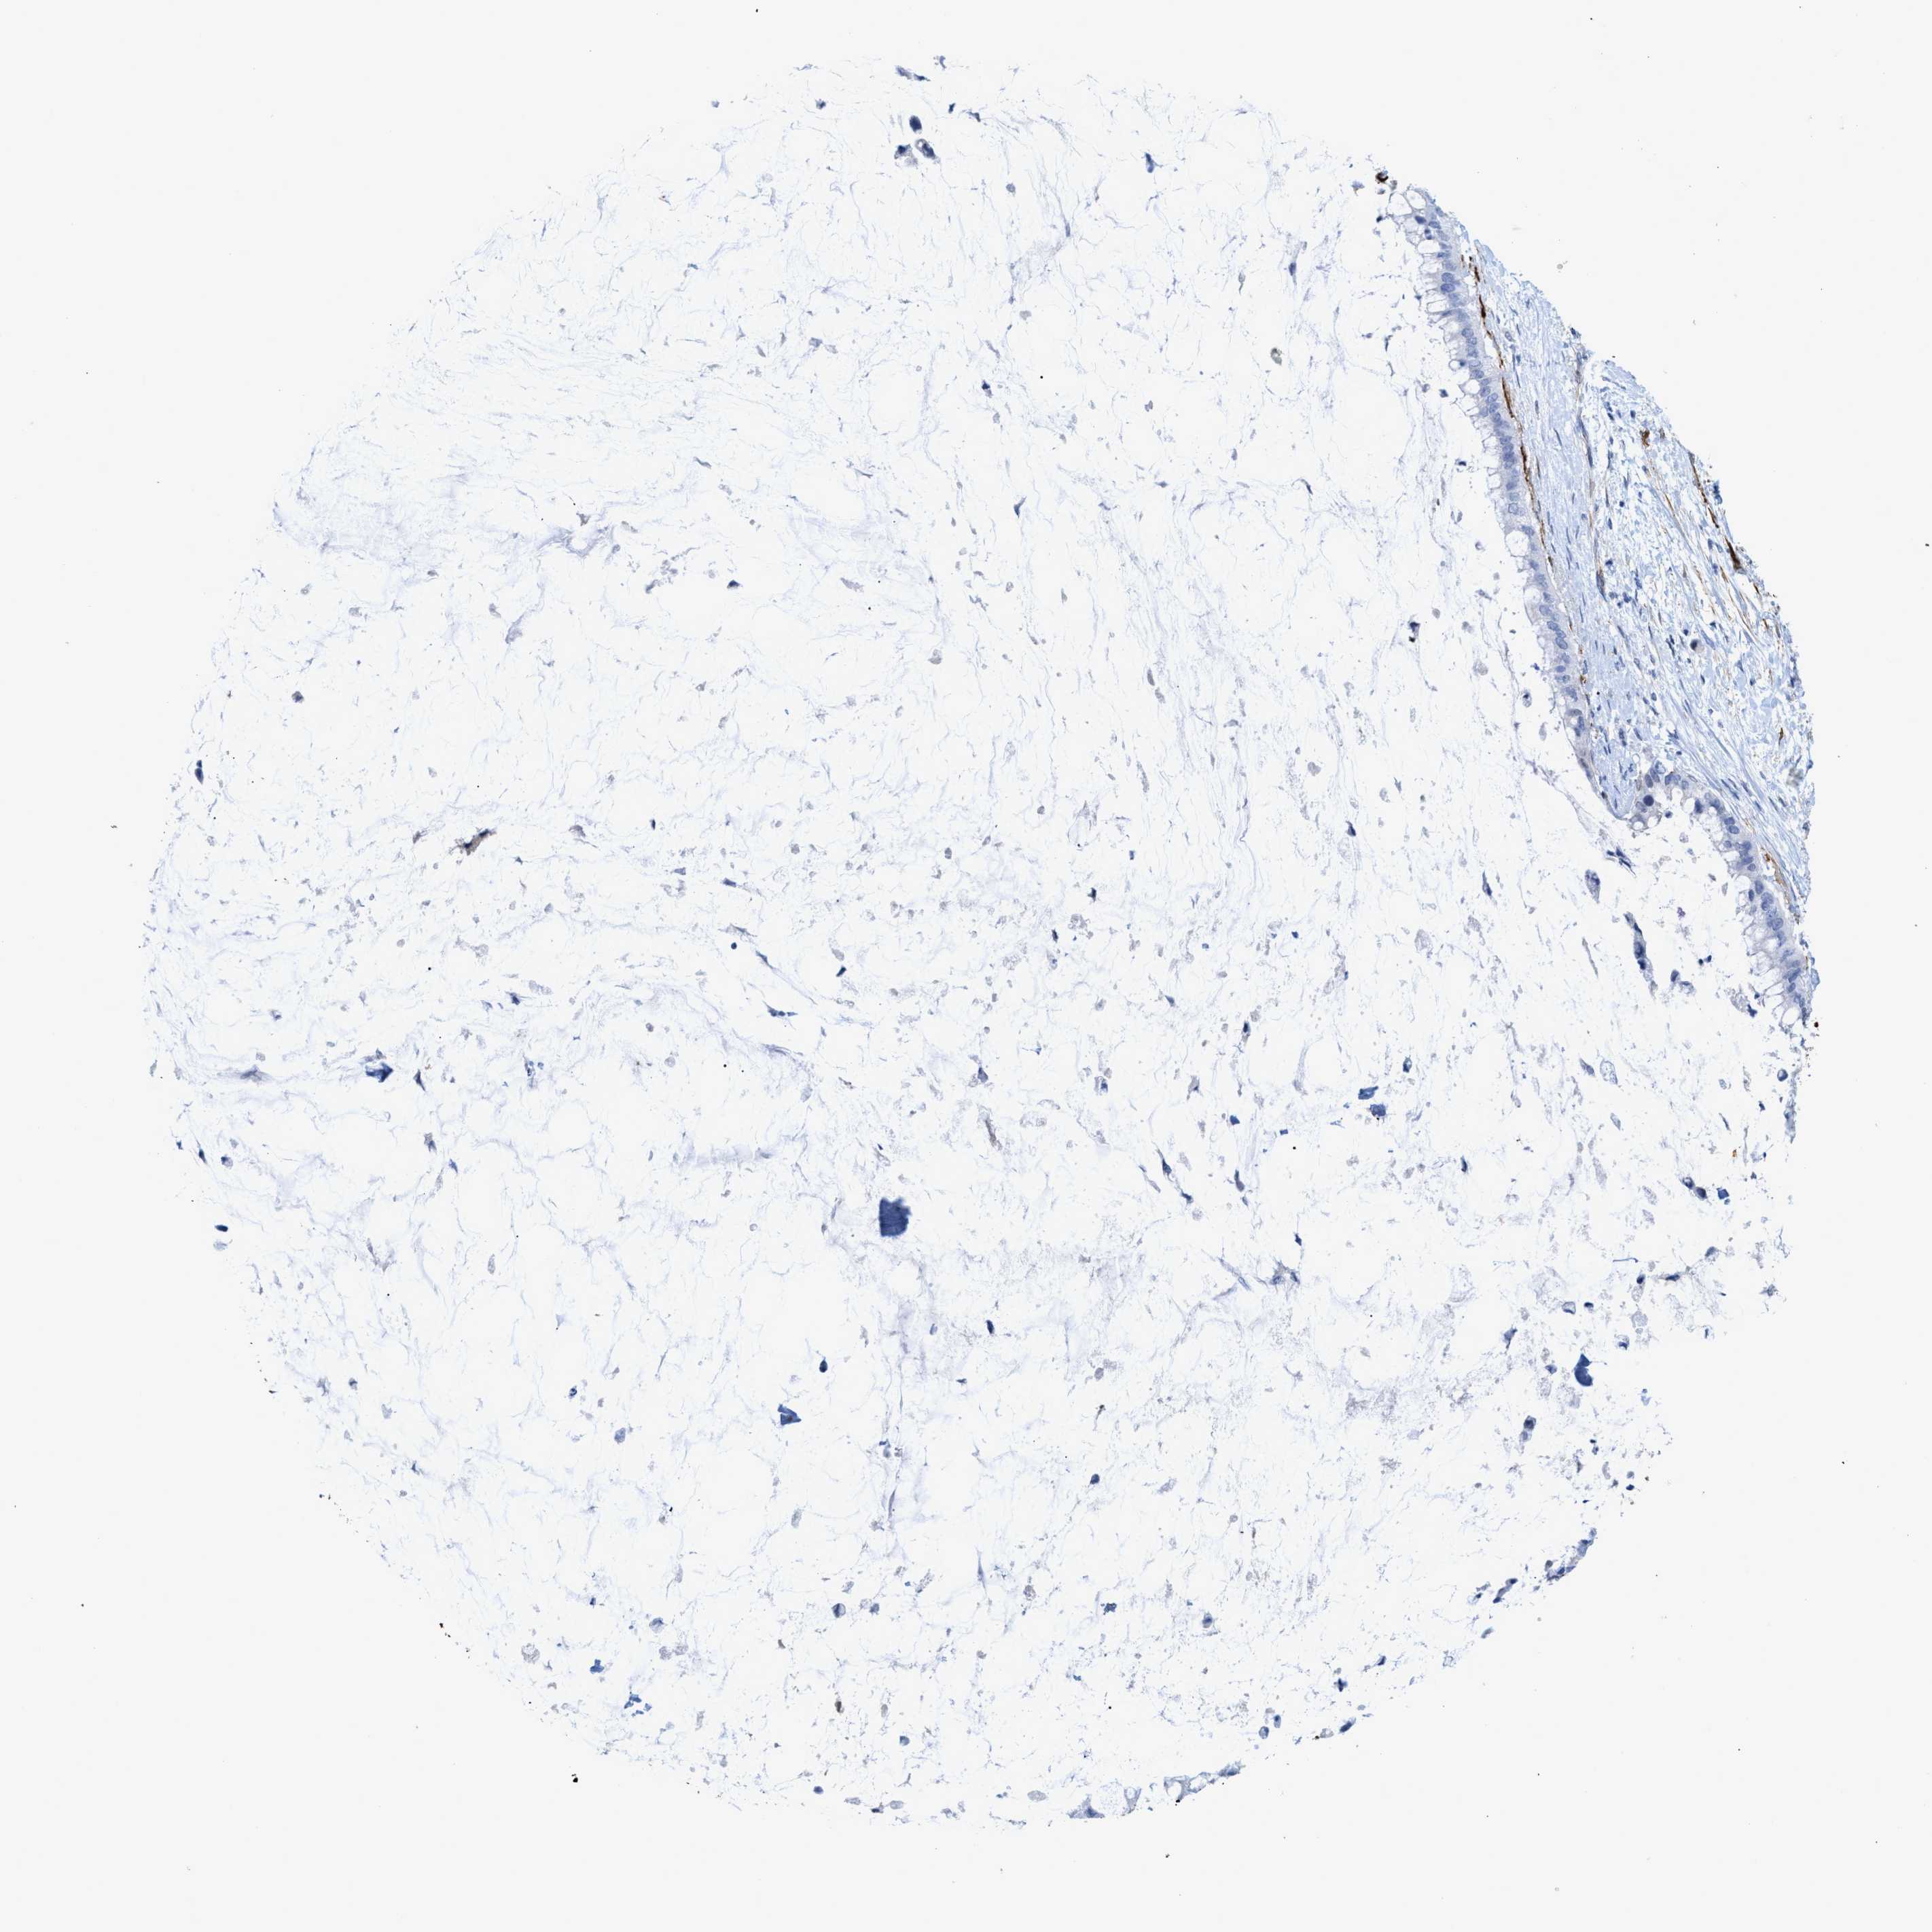

PANCREATIC CANCER - Protein expressioni

A mouse-over function shows sample information and annotation data. Click on an image to view it in a full screen mode. Samples can be filtered based on level of antibody staining by selecting one or several of the following categories: high, medium, low and not detected. The assay and annotation is described here.

Note that samples used for immunohistochemistry by the Human Protein Atlas do not correspond to samples in the TCGA dataset.

Antibody stainingi

Antibody staining in the annotated cell types in the current human tissue is reported as not detected, low, medium, or high, based on conventional immunohistochemistry profiling in selected tissues. This score is based on the combination of the staining intensity and fraction of stained cells.

Each image is clickable and will lead to virtual microscopy that enables deeper exploration of all samples and also displays staining intensity scores, fraction scores and subcellular localization as well as patient and tissue information for each sample.

Antibody HPA019467

Antibody HPA061657

Antibody CAB001447

Staining

High

Medium

Low

Not detected

Intensity

Strong

Moderate

Weak

Negative

Quantity

>75%

75%-25%

<25%

None

Location

Nuclear

Cytoplasmic/membranous

Cytoplasmic/membranous,nuclear

Adenocarcinoma, NOS